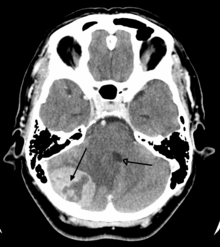

Medical imaging plays a central role in the diagnosis of brain tumors. Early imaging methods – invasive and sometimes dangerous – such as pneumoencephalography and cerebral angiography have been abandoned in favor of non-invasive, high-resolution techniques, especially magnetic resonance imaging (MRI) and computed tomography (CT) scans, though MRI is typically the reference standard used.[37] Neoplasms will often show as differently colored masses (also referred to as processes) in CT or MRI results.

This is because these tumors disrupt the normal functioning of the BBB and lead to an increase in its permeability. More recently, advancements have been made to increase the utility of MRI in providing physiological data that can help to inform diagnosis and prognosis. Perfusion Weighted Imaging (PWI) and Diffusion Weighted Imaging (DWI) are two MRI techniques that reviews have been shown to be useful in classifying tumors by grade, which was not previously viable using only structural imaging.[38] However, these techniques cannot alone diagnose high- versus low-grade gliomas, and thus the definitive diagnosis of brain tumor should only be confirmed by histological examination of tumor tissue samples obtained either by means of brain biopsy or open surgery. The histological examination is essential for determining the appropriate treatment and the correct prognosis. This examination, performed by a pathologist, typically has three stages: interoperative examination of fresh tissue, preliminary microscopic examination of prepared tissues, and follow-up examination of prepared tissues after immunohistochemical staining or genetic analysis.